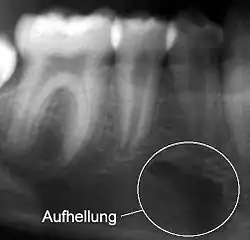

Aufhellung

Eine Verschattung (auch Radioopazität) ist ein heller und eine Aufhellung (Radioluzenz) ein dunkler Bereich auf einem Röntgenbild.[1] Grund ist die unterschiedliche Röntgenopazität von Gewebearten.

Da die Begriffe aus der Ära des Fluoreszenzradiographie beibehalten wurden, liegt ein scheinbares Paradoxon vor. Es wird also ein Bereich auf dem Röntgenfilm, der heller ist, als er sein sollte, verschattet genannt und ein Bereich, der dunkler ist, als er sein sollte, aufgehellt genannt.